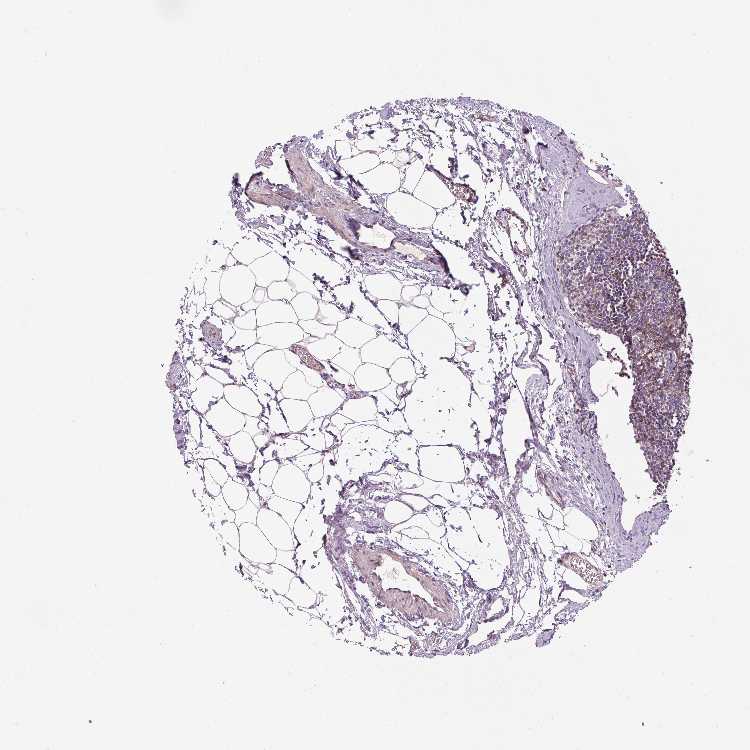

TISSUE PRIMARY DATA LYMPH NODE Show tissue menu

LYMPH NODE - Antibody stainingi

Antibody staining in the annotated cell types in the current human tissue is reported as not detected, low, medium, or high, based on conventional immunohistochemistry profiling in selected tissues. This score is based on the combination of the staining intensity and fraction of stained cells.

Each image is clickable and will lead to virtual microscopy that enables deeper exploration of all samples and also displays staining intensity scores, fraction scores and subcellular localization as well as patient and tissue information for each sample.

Antibody HPA054844

Germinal center cells Low

Non-germinal center cells Medium

Information about each individual sample is listed below, including gender, age, a tissue section image and estimated fractions of cell types. nTPM (normalized transcripts per million) values give a quantification of the gene abundance which is comparable between different genes and samples.

Male, age 34

Lymph node sample 173

nTPM: 3.5

Cell types%

Lymphocytes:

85

Other cell types:

15

overview

Female, age 29

Lymph node sample 174

nTPM: 3.9

95

5